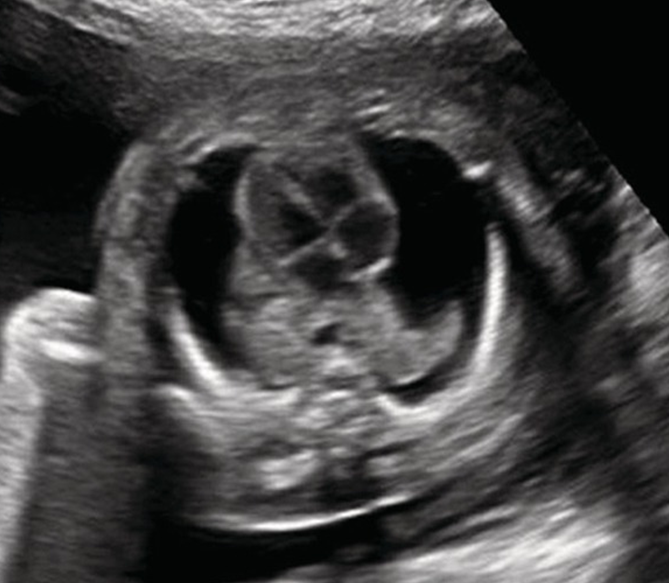

What view is this?

Crisscross view

Long-axis Outflow Tract/ LVOT